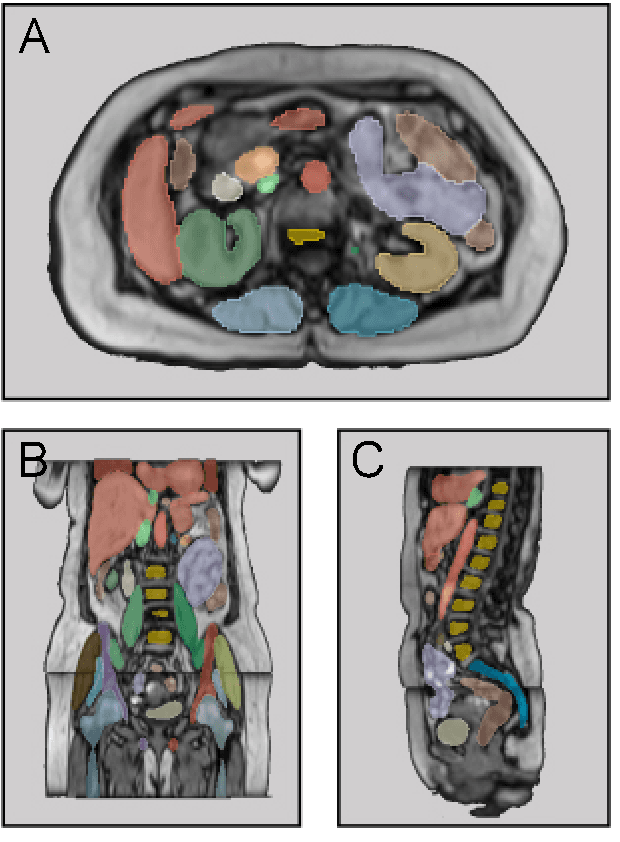

Abstract:Purpose: To introduce a deep learning model capable of multi-organ segmentation in MRI scans, offering a solution to the current limitations in MRI analysis due to challenges in resolution, standardized intensity values, and variability in sequences. Materials and Methods: he model was trained on 1,200 manually annotated MRI scans from the UK Biobank, 221 in-house MRI scans and 1228 CT scans, leveraging cross-modality transfer learning from CT segmentation models. A human-in-the-loop annotation workflow was employed to efficiently create high-quality segmentations. The model's performance was evaluated on NAKO and the AMOS22 dataset containing 600 and 60 MRI examinations. Dice Similarity Coefficient (DSC) and Hausdorff Distance (HD) was used to assess segmentation accuracy. The model will be open sourced. Results: The model showcased high accuracy in segmenting well-defined organs, achieving Dice Similarity Coefficient (DSC) scores of 0.97 for the right and left lungs, and 0.95 for the heart. It also demonstrated robustness in organs like the liver (DSC: 0.96) and kidneys (DSC: 0.95 left, 0.95 right), which present more variability. However, segmentation of smaller and complex structures such as the portal and splenic veins (DSC: 0.54) and adrenal glands (DSC: 0.65 left, 0.61 right) revealed the need for further model optimization. Conclusion: The proposed model is a robust, tool for accurate segmentation of 40 anatomical structures in MRI and CT images. By leveraging cross-modality learning and interactive annotation, the model achieves strong performance and generalizability across diverse datasets, making it a valuable resource for researchers and clinicians. It is open source and can be downloaded from https://github.com/hhaentze/MRSegmentator.